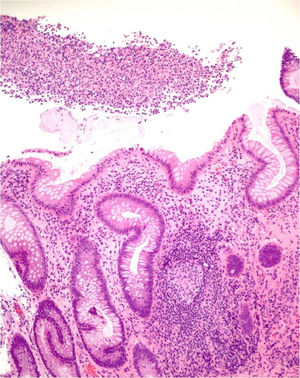

En 9 pacientes con afectación anorrectal se practicó una rectosigmoidoscopia, que demostró úlceras extensas superficiales de límites geográficos en el canal anal y en la ampolla rectal (fig. 4). En las histologías de estos pacientes predominaron los patrones granulomatosos con infiltrados crónicos inespecíficos, asociados a criptitis aguda en 3 de los casos (fig. 5). No se evidenciaron microorganismos en las biopsias y las inmunohistoquímicas para citomegalovirus y Treponema pallidum fueron negativas. En el caso 1 se realizó una resonancia nuclear magnética que demostró edema de la mucosa rectal con obliteración de la luz con extensión al mesorrecto, asociado a múltiples adenopatías en las cadenas pararrectales e hipogástricas. En los casos de LGV clásico la ecografía fue de utilidad para demostrar y hacer un seguimiento de las adenopatías inflamatorias inguinales, así como de los abscesos y de las fístulas. En todos los casos se identificó el serovar L2 de C. trachomatis (con referencia en genbank CP002682.1) como agente etiológico.

El LGV anorrectal cursa habitualmente como una proctitis severa, en la que suele predominar el exudado anal, en ocasiones sanguinolento13. El tenesmo rectal es uno de los síntomas principales, y puede ir acompañado de malestar general y de febrícula con pérdida de peso si se mantiene en el tiempo3. La afectación de los ganglios pararrectales y la ausencia de afectación de los inguinales hace imposible demostrar la afectación linfática en la exploración clínica. La resonancia nuclear magnética puede demostrar la afectación de la pared rectal y de tejidos circundantes, así como la extensión a los ganglios linfáticos4. El desconocimiento del síndrome por parte del clínico puede llevar a confusión al radiólogo, que puede interpretar los hallazgos como de origen tumoral14, como ocurrió en nuestro primer caso. La magnitud de los síntomas obliga al especialista no familiarizado con el cuadro a la solicitud de endoscopias en las que las imágenes y las histologías se pueden asemejar a la enfermedad inflamatoria intestinal15. La toma de una muestra para el estudio microbiológico de los exudados o del tejido de la biopsia y la evaluación mediante técnicas de secuenciación de ácidos nucleicos permiten identificar los serovares linfáticos de C. trachomatis16, pero estas técnicas están disponibles solamente en laboratorios especializados. La toma del exudado es obligada en pacientes con proctitis sintomáticas y antecedentes de sexo anal receptivo no protegido, sobre todo si se trata de pacientes seropositivos para el VIH. La histología es indistinguible de la enfermedad inflamatoria intestinal15, pero permite realizar el diagnóstico diferencial con otras proctitis de origen infeccioso y con los carcinomas anorrectales. El papel del dermatólogo en el diagnóstico del LGV y la formación continuada que puede ofrecer a otros especialistas que tratan habitualmente a estos pacientes es fundamental para el correcto manejo de la infección y para evitar pruebas complementarias innecesarias.